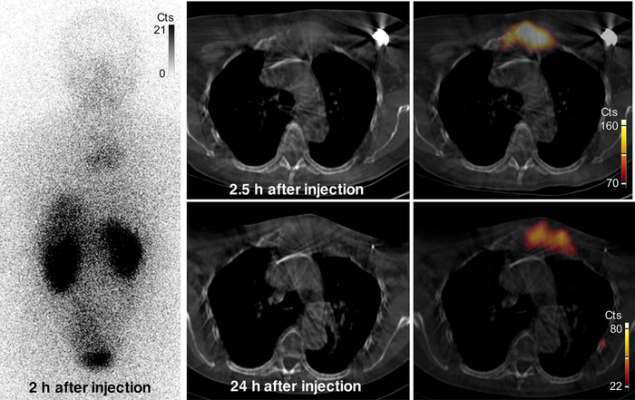

Images of uptake in bone metastasis in patient 2. Anterior whole-body (left) and SPECT/CT (right) images show uptake of 131I-GMIB-anti-HER2-VHH1 at level of large lytic bone metastasis, with soft-tissue component at sternal bone both at 2.5 h and at 24 h after injection. Small differences in area of uptake are explained by differences in patient positioning (arms up at 2.5 h and arms down at 24 h, to maximize patient comfort). Cts = counts. Image created by M. Keyaerts, University Hospital of Brussels (UZ Brussel), Belgium.

131I-GMIB-anti-HER2-VHH1 was found to be safe and stable after administration and to clear rapidly from the blood in healthy volunteers. The tracer accumulated in metastatic sites of patients with HER2-positive breast cancer.